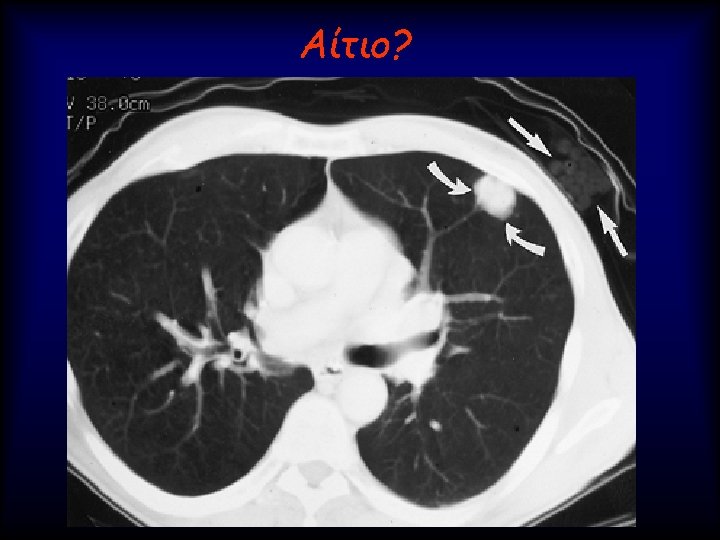

Lung nodule analysis • Evaluating Pulmonary Nodules Pulmonary nodules ≤ 4 mm have a

Lung nodule analysis • Evaluating Pulmonary Nodules Pulmonary nodules ≤ 4 mm have a low risk of being cancerous; • nodules between 4 -8 mm are of intermediate risk for cancer; follow up CT scans for both categories are recommended on different schedules • Pulmonary nodules >8 mm and mixed solid/ground glass nodules are suspicious for cancer; percutaneous needle aspiration biopsy (PNAB), positron emission tomography (PET), or video assisted thoracic surgery (VATS) should be considered